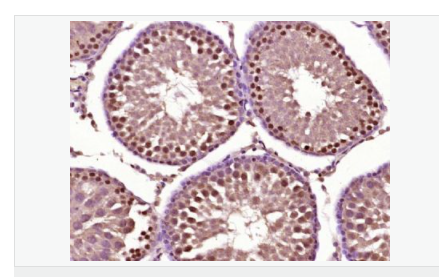

產品介紹Acrosin is the major proteinase present in the acrosome of mature spermatozoa. It is a typical serine proteinase with trypsin-like specificity. It is stored in the acrosome in its precursor form, proacrosin. The active enzyme functions in the lysis of the zona pellucida, thus facilitating penetration of the sperm through the innermost glycoprotein layers of the ovum. The mRNA for proacrosin is synthesized only in the postmeiotic stages of spermatogenesis. In humans proacrosin first appears in the haploid spermatids.

產品應用WB=1:500-2000 ELISA=1:5000-10000 IHC-P=1:100-500 IHC-F=1:100-500 Flow-Cyt=1ug/Test IF=1:50-200 (石蠟切片需做抗原修復)

細胞定位細胞核 細胞漿

免 疫 原KLH conjugated synthetic peptide derived from human Acrosin heavy chain:201-300/421